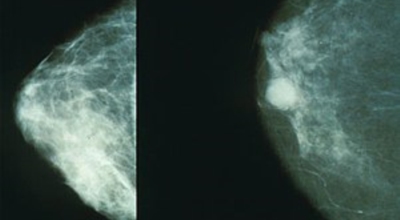

개인마다 초기증상은 다르게 나타날 수 있어요. 유방암은 우리나라 여성암 1위인만큼 많은 여성분들이 유방암에 대해 관심이 많아 검사를 많이 하는 추세입니다. 스트레스를 많이 받는 젊은 여성들도 유방 통증으로 진단을 받는 경우가 늘고 있다고 해요. 경우에 따라서는 유방암 초기증상이 없을 수도 있답니다. 유방암 자가검진 후 증상이 발견된다면 빨리 병원에 방문하는 편이 좋아요.

보통 응어리가 잡히는 분들의 40%는 물혹으로 가벼운 질병으로 바로 치유가 되는 경우가 많은데요 20~30%의 확률로 유방암 초기증상일 가능성이 있다고 하죠. 따라서 매일같이 자신의 가슴을 마사지 해주시다 어느 날 응어리가 잡히게 된다면 유방암 검사 초기에 받아 보시기를 권해 드립니다.